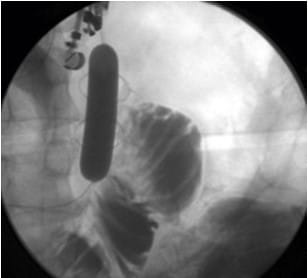

EUS-guided hemostasis introduces an innovative approach to managing gastric varices through coil embolization and/or glue injection. This technique has emerged as a clinically effective method for controlling bleeding, demonstrating promising treatment outcomes. The ability to directly visualize and target the treatment area offers a significant advantage over traditional methods, marking a new era in gastroenterological care.